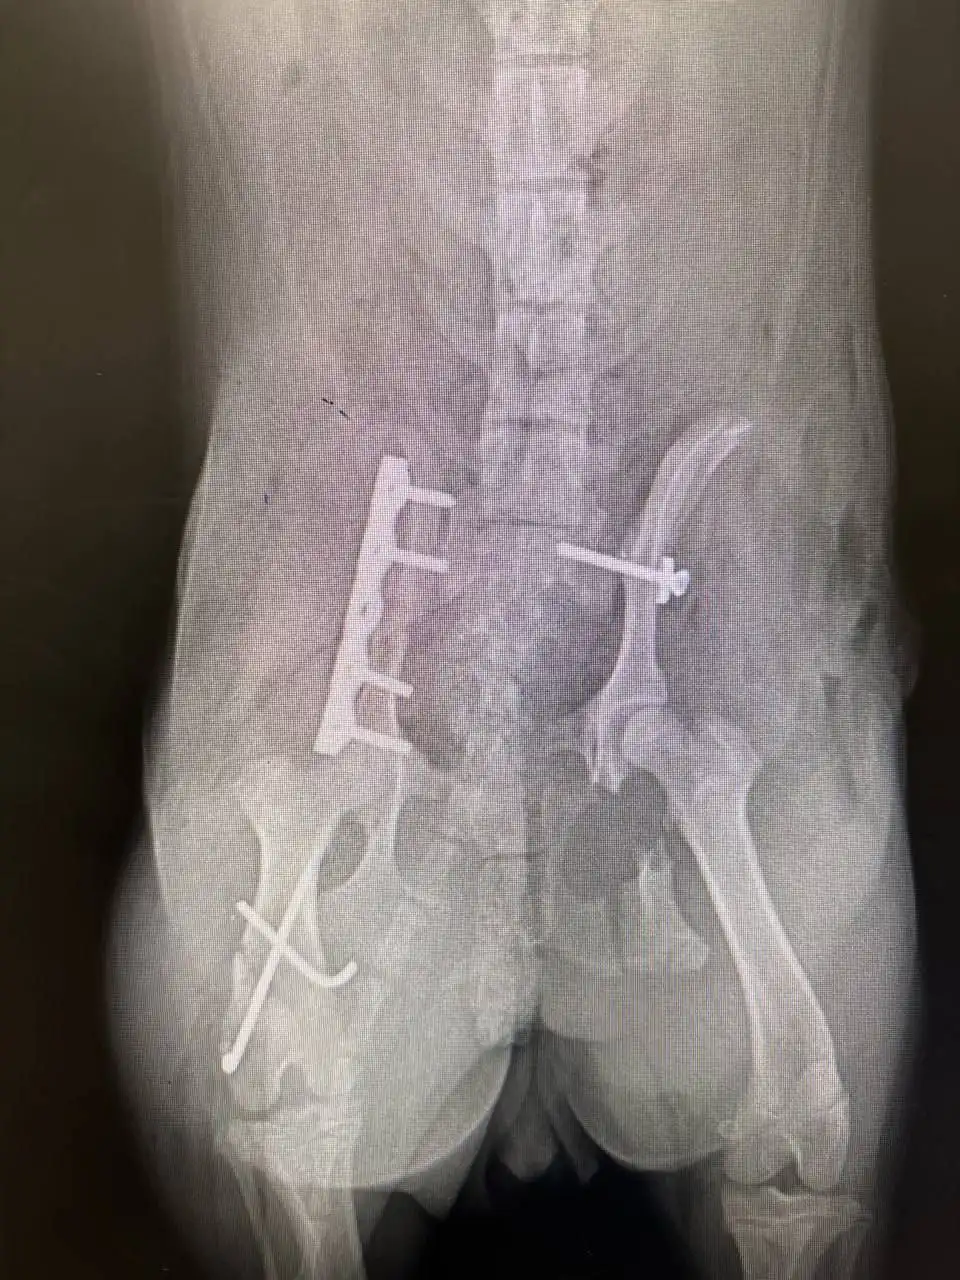

Друзья, просим вашей помощи. Недавно Милку сбила машина, и травмы оказались очень серьёзными, сломан таз, бедро. А ведь она очень маленькая, безобидная собачка, и ей всего лишь 6 месяцев. Милку уже отвезли в Казань, где врачи провели срочно сложную операцию. Но лечение и операция стоят больших денег. Мы обращаемся ко всем неравнодушным. Любая помощь — даже самый небольшой перевод — поможет закрыть долг перед клиникой. Если нет возможности помочь финансово, пожалуйста, сделайте репост, чтобы как можно больше людей узнали о Милке. Давайте вместе поможем Милке выжить и вернуться к жизни без боли. В Ишеевке её ждёт сестрёнка Вейка, с которой она неразлучалась с самого рождения. Заранее спасибо каждому, кто откликнется. С пометкой "для Милки из Ишеевки"